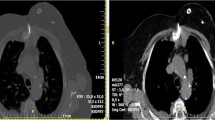

Thermal ablation is used to destroy tumors through the direct application of heat- or cold-based energies [13, 26,27,28,29], delivered percutaneously with the exception of High-intensity focused ultrasound (HIFU). Thermal ablation can be performed with a curative or palliative intent (Fig. 3).

Curative treatment. a Single metastasis (white arrow) of the rib in a 45-year-old patient with a history of breast cancer. b The metastasis was FDG-avid on PET-CT (white arrow). c After cryoablation, d effective local tumor control was noted at 12-month PET-CT follow-up. Palliative treatment. e Painful (VAS 9/10) T5 FDG-avid metastasis from gastric cancer in a 68-year-old patient. f Bilateral bipolar RFA was performed with thermal monitoring at the level of the posterior wall (white arrow) and hydro-dissection of the epidural space (black arrow); g, h in the end, vertebroplasty was performed to prevent a secondary vertebral body collapse. Pain relief (5/10) was noted by the 15th postoperative day